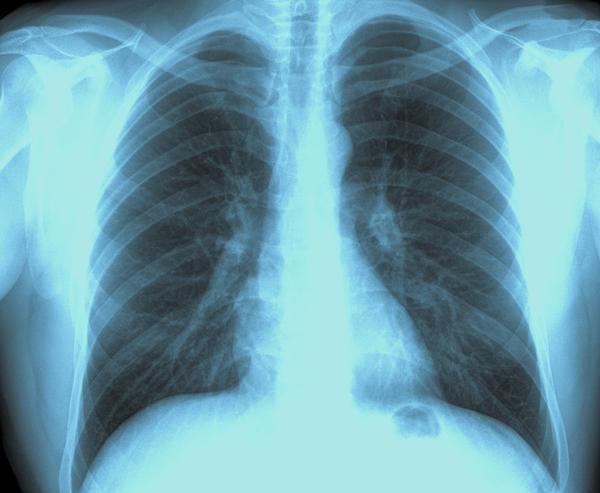

- рентген грудной клетки;

Важно отметить, что возраст пациента в таких ситуациях не играет никакой роли. В случаях образования раковых опухолей одним из основных способов диагностирования заболевания является рентгеновское исследование органов, расположенных в грудной полости. В качестве дополнительных методов диагностики используют следующие:

- УЗИ органов грудной клетки;

- компьютерную томографию;

- магнитно-резонансную томографию;

- биопсию.